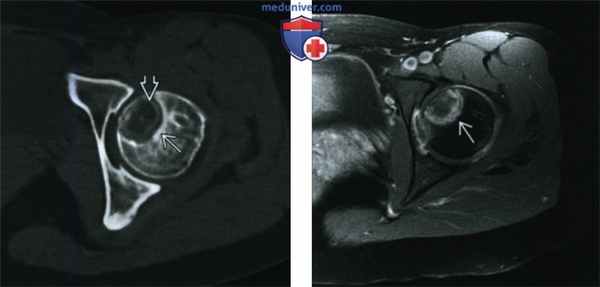

(Слева) КТ, аксиальная проекция, без контрастного усиления: светлоклеточная хондросаркома. Хорошо отграниченный эпифизарный очаг имеет склерозированный край и содержит сла-бовыраженный хрящевой матрикс. Данные признаки не позволяют проводить дифференциальную диагностику с хондробластомой, наличие которой статистически более вероятно.

(Справа) МРТ, аксиальная проекция, режим Т1, с подавлением сигнала от жира, с контрастным усилением: у этого же пациента визуализируется толстый неравномерный ободок контрастного вещества. Учитывая данные признаки здесь также необходимо проводить дифференциальную диагностику между хондробластомой и светлоклеточной хондросаркомой (которая получила гистологческое подтверждение).